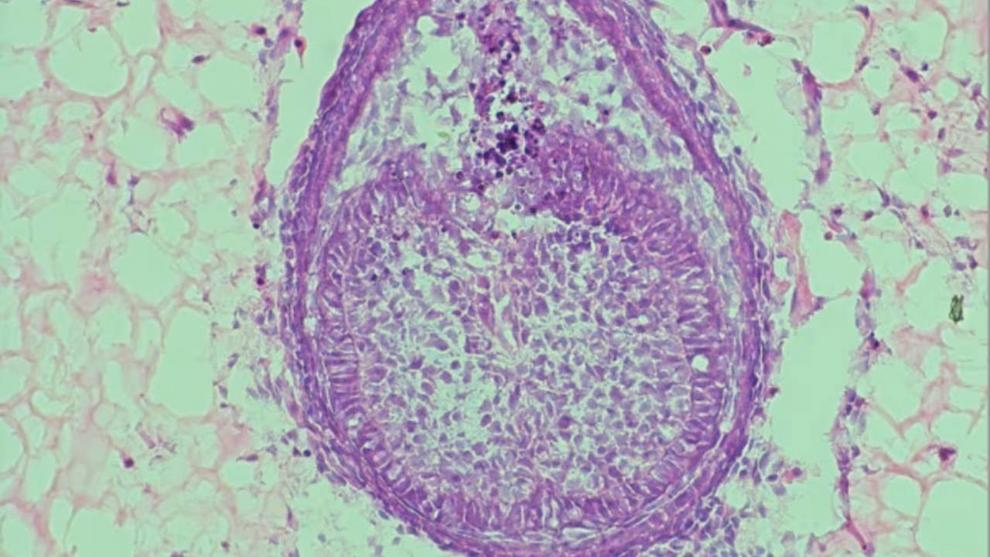

به گفته ولپونی، ایده رشد دندان در محیط مصنوعی به دهه ۱۹۸۰ برمی‌گردد. در پژوهش سال ۲۰۱۳، او و تیمش نخستین بار سلول‌های لثه بزرگسال انسان را با سلول‌های پیش‌ساز دندان از جنین موش ترکیب کردند تا جوانه‌ای از دندان بسازند.

این محیط رشد که با عنوان «اسکفلد» (Scaffold) شناخته می‌شود، در شکل‌گیری دندان نقشی حیاتی دارد. تمرکز پژوهش اخیر ولپونی نیز بر توسعه همین ساختار بوده است. در حالی‌که نسخه ۲۰۱۳ از کلاژن ساخته شده بود، نسخه جدید از هیدروژل استفاده می‌کند؛ ماده‌ای پلیمری با درصد بالای آب که محیطی طبیعی‌تر برای رشد سلول‌ها فراهم می‌آورد.

«سلول‌های جنین موش را جمع‌آوری می‌کنیم، با هم ترکیب می‌نماییم و توده‌ای کوچک از سلول‌ها (Pellet) می‌سازیم. سپس آن را داخل هیدروژل تزریق کرده و حدود هشت روز رشد می‌دهیم.»